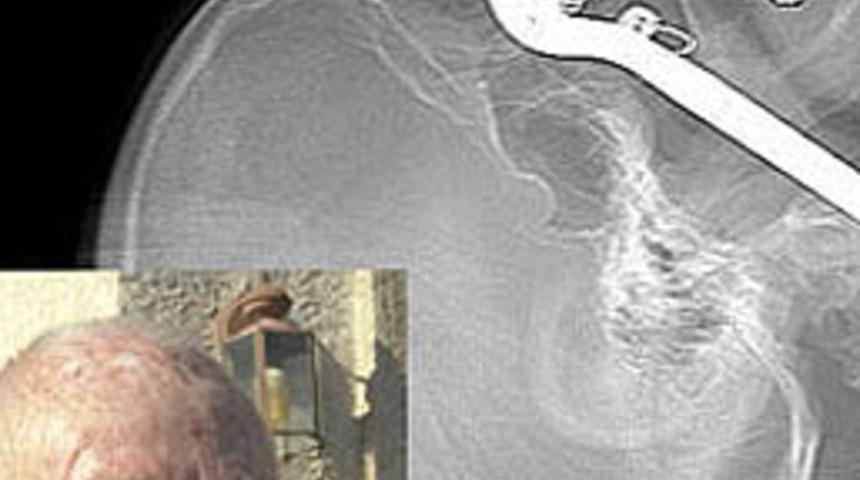

ABD'de göz çukuruna bahçe makası saplanan ve boğazına kadar giren 86 yaşındaki Leroy Luetscher, mucize kabilinden gözünde veya vücudunda kalıcı hasar olmadan kurtuldu.

Arizona eyaletindeki Tucson kentindeki bahçesinde çalışan Leroy Luetscher, düşürdüğü makası yerden almak için eğilirken düştü. Makasın elle tutulan kısmı, Luetscher'in göz çukurundan girerek boğazındaki beyne kan götüren damarlara saplandı.

Luetscher, göz çukuruna saplanan bahçe makası ile Arizona Üniversitesi Hastanesi'ne kaldırıldı. Doktorlar, makası çıkarırken Luetscher'in göz çukurunu da metal kafes ile tedavi ederek yaşlı adamın gözünü kurtarmayı başardı.

Yaşlı adamın gözünde kalıcı bir hasar olmadığı belirtildi. Kameraların karşısına geçen Leroy Luetscher, kendisini eski sağlığına kavuşturan doktorlara teşekkür etti.